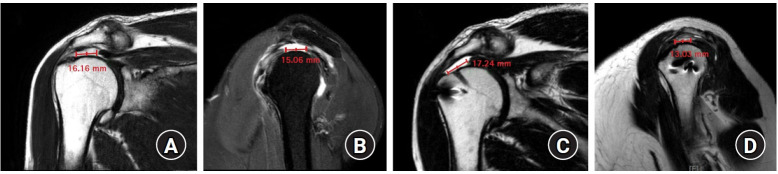

The maximum mediolateral lengths and AP widths of pre- and postoperative tears were measured using the protocol of Davidson et al. (Fig. 3) [23], and variance of tear dimension was calculated by subtracting the preoperative dimension from the postoperative dimension for mediolateral lengths and AP widths, respectively. Two orthopedic physicians (MSJ and KLK) independently reviewed the radiographs and magnetic resonance images to assess the measurement variables. The intraclass correlation coefficient was used to assess interobserver reliabilities for agreement regarding measured values. Correlation was determined to be poor if the coefficient was <0.4, marginal if ≥0.4 and ≤0.75, and good if >0.75 [24].

Fig. 3.

Measuring pre- and postoperative tears using the magnetic resonance imaging (MRI) protocol of Davidson et al. [23]. (A) Preoperative maximal mediolateral length on T2-weighted coronal oblique MRI view. (B) Preoperative anterior to posterior widths on T2-weighted sagittal oblique MRI view. (C) Postoperative maximal mediolateral length on T2-weighted coronal oblique MRI view. (D) Postoperative anterior to posterior widths on T2-weighted sagittal oblique MRI view.